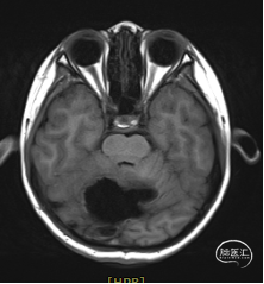

术前MRI

现病史:患者18个月前无明显诱因出现间断头痛,休息后可缓解,开始未予重视,未行特殊治疗。1周前患者无明显诱因出现恶心、呕吐,就诊于当地医院,行颅脑MRI提示:小脑囊实性占位性病变,首先考虑毛细胞星型细胞瘤。现患者为求进一步治疗就诊于我院,门诊以“脑肿瘤”收入院。患者自发病以来神志清,精神可,饮食睡眠正常,二便如常,体重未见明显下降。

小脑肿瘤(毛细胞型星形细胞瘤?)